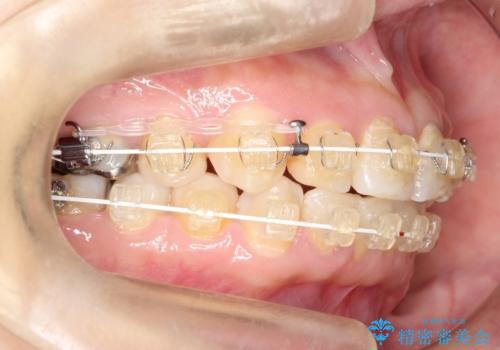

【ワイヤー矯正】前歯が出てるのをなおしたい。

- 矯正装置

- 審美装置

- 前歯の凸凹を主訴に来院されました。